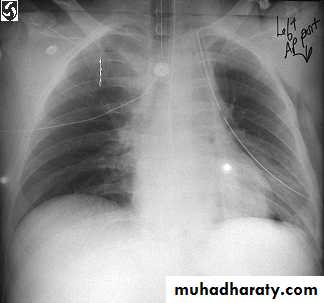

Chest X-ray;Shows the sharply defined edge of the deflated lung with complete translucency (no lung markings) between this and the chest wall. Chest X-rays also show the extent of any mediastinal displacement and give information regarding the presence or absence of pleural fluid and underlying pulmonary disease.